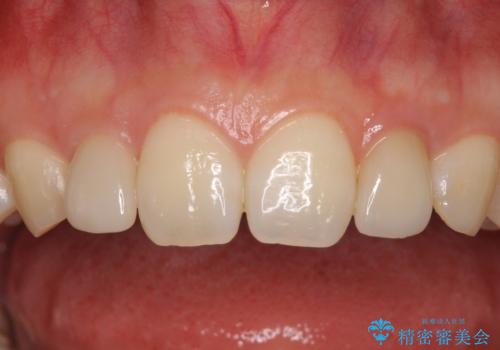

着色の原因として、湿気の多い環境で接着操作を行うと、境目に細かいギャップができてしまうことが考えられます。

接着の際にはラバーダムを使用して、乾燥した環境を整えて処置を行いました。